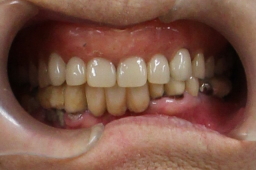

| 従って、喫煙者等で歯ぐきが退縮してインプラントが露出しても、感染に強いのです。 下記は喫煙者のため、自分の歯の部分の歯ぐきもインプラントの部分の歯ぐき退縮。 しかし、インプラントは感染していません。インプラント植立約10年後(喫煙者) |

歯ぐきが退縮して自分の歯根やインプラント が露出していますが、インプラントに感染はなし。 =タバコは自分の歯やインプラントもダメにします= |